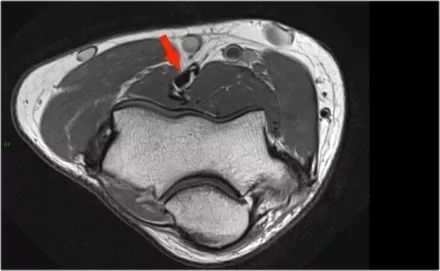

下面是另一种情况。在矢状图像上,我们不确定可能的撕裂。也许只有一些肌腱炎或肌腱炎。轴向图像显示部分撕裂(红色箭头)。

始终确保你的轴向扫描一直到结节,因为你太早停止,就像在这种情况下,你只会看到增厚的肌腱和一些液体,但你不确定可能的撕裂。